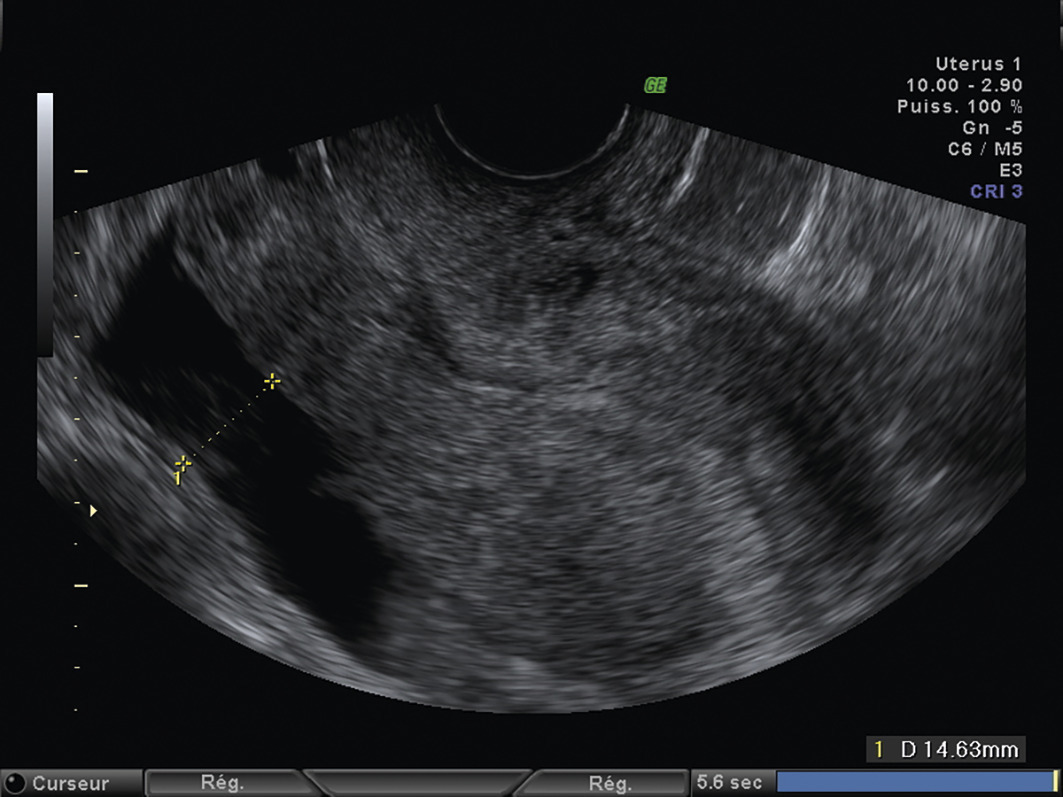

L’échographie, indispensable, doit examiner le pelvis mais aussi l’abdomen. Elle est donc réalisée par voie endovaginale, sus-pubienne et abdominale. On peut visualiser une masse latéro-utérine (fig. 1). Au sein de cet hématosalpinx, un sac gestationnel peut être visible, voire un embryon (fig. 2) ayant parfois une activité cardiaque positive. Le passage de la sonde à ce niveau est douloureux.

Remerciements au Dr Gilles Grange, maternité Port-Royal, Paris pour les figures 1, 2 et 3.